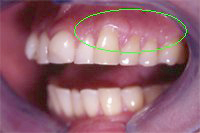

Ein 31 Jahre alter Patient zeigt einen starke Zahnfleisch-Rückgang im Oberkiefer (Abb. 1 und 3) und wir beschliessen, diese Rezessionen zu behandeln.

Der Erfolg der Behandlung ist deutlich in den Abb. 2 und 4 zu sehen. Sehr augenfällig konnte die Situation um den Eckzahn im linken Oberkiefer verbessert werden (vergleiche dazu Abb. 3 vorher und Abb. 4 nachher).